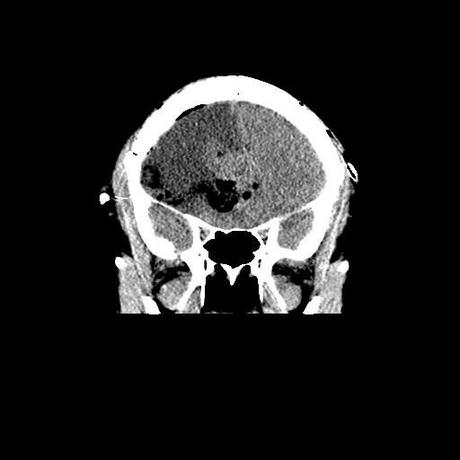

Corte coronal post quirúrgico, adecuada resección de lesión. Coronal CT scan, showing a proper tumor resection